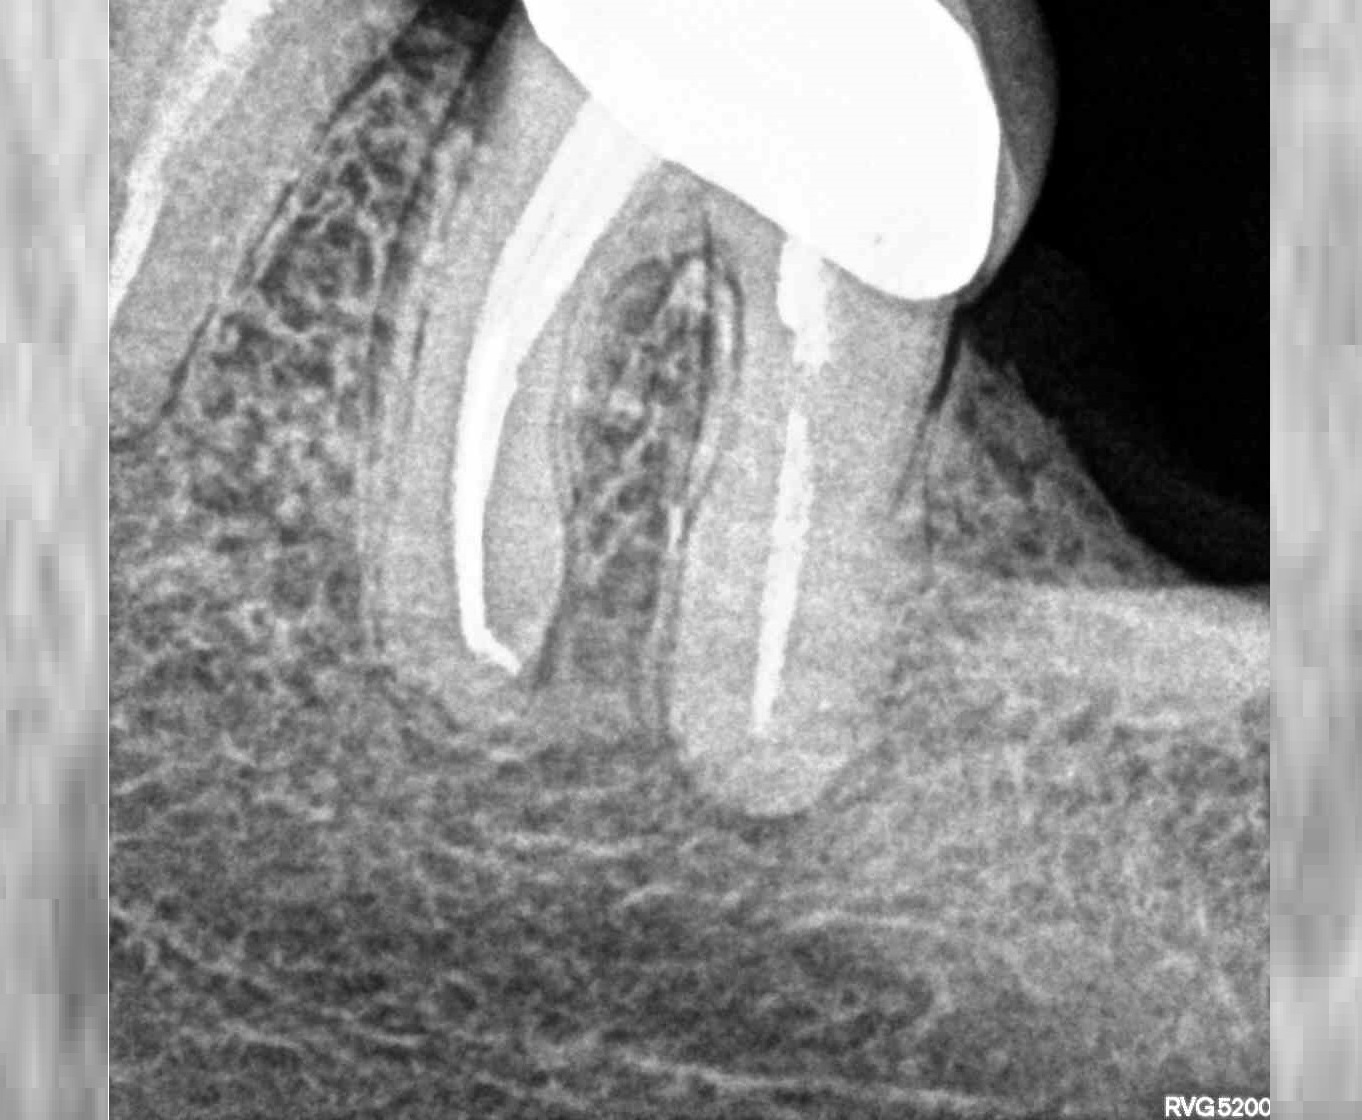

- Лечение пульпита

Проблема

Пациент обратился в клинику с жалобами на боли ноющего характера, усиливающиеся при надкусывании на зуб, реакция на холодное и горячее, так же на наличие глубокой кариозной полости, застревание пищи в зубе.Решение

Произведено пломбирование корневых каналов. Наблюдается уменьшение воспалительного процесса. Пациент может жевать, нет реакции на горячее и холодное. Лечение прошло успешно.Оставьте заявку - перезвоним в течении 15 минут!